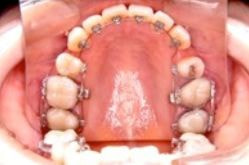

金属(メタル)ブラケット

メリット

* 装置についた汚れがわかりやすい

* 歯みがきしやすい

デメリット

* 目立ちやすい